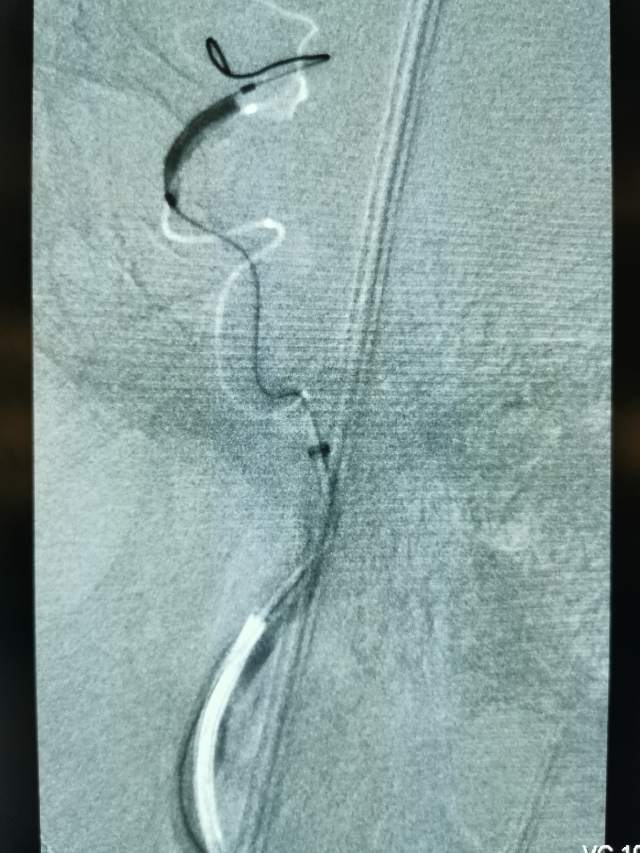

我们全面评估后,基于安全考虑,住院期间先后完成了两次外科干预,帮助患者将已经闭塞的血管重新开通,“满江红”的大脑终于变成了“半江红”,第一次外科干预后,保姆说改变好明显;第二次干预后的第二天,患者眼神明亮、对答如流、思维敏捷、面带微笑,在病房里走来走去,俨然像巡视病房的医生,很是拉风。